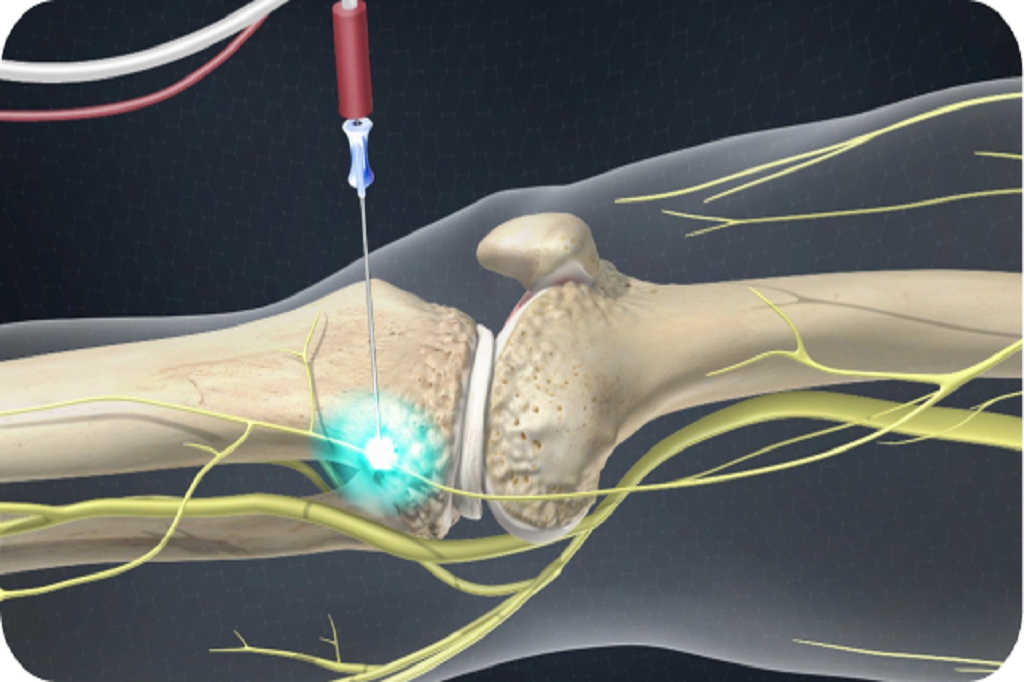

Durable relief for spinal or knee pain, done after a positive diagnostic block to disrupt nerve signals.